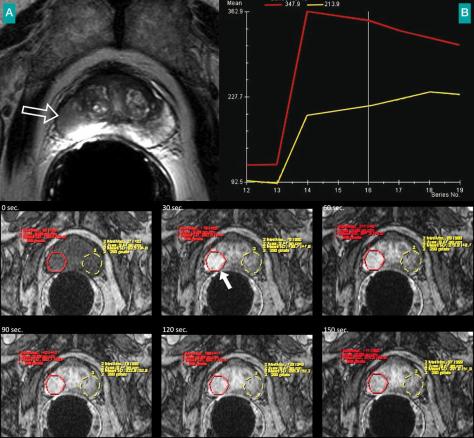

Patient de 67 ans adressé pour élévation du PSA à 7,8 ng/mL. Biopsies positives au niveau du lobe droit avec un score de Gleason 7. (A) Imagerie par résonance magnétique, séquence pondérée en T2. Lésion nodulaire de la prostate périphérique au niveau du lobe droit (flèche ouverte), ne franchissant pas la capsule. (B) Les séquences dynamiques montrent un rehaussement intense et précoce de la lésion à 30 s (flèches pleines), confirmé par les courbes de rehaussement. La courbe rouge correspond au côté pathologique.